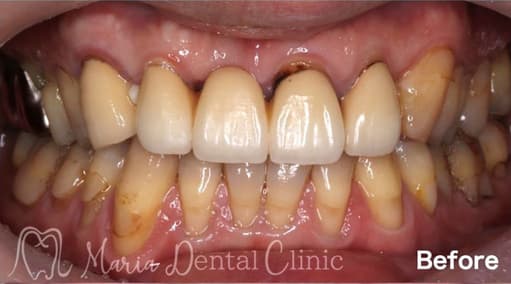

インプラントを守るために強い歯茎を移植(FGG)

インプラントの周りの硬い歯茎が失われた患者様に対する、歯茎再生の手術(付着歯肉を増やすための歯茎の移植)を行った症例です。

before

after

治療内容 遊離歯肉移植術(FGG)

治療期間 3ヶ月(移植した歯茎が落ち着くまで)

治療回数 1回(他、抜糸や経過観察を除く)

治療費用 137,500円(税込)

症例から言えること

抜歯すると、骨のボリュームと歯茎のボリュームが下がるため、強い歯ぐきも同時に失われます。その結果、インプラントを埋入するときに必要な付着歯肉が得られない(3mm以下)状態になってしまうケースは少なくありません。この症例の患者様のように硬い歯茎が失われていると、インプラントが長持ちしないことが多くの研究で明らかになっています。インプラントは虫歯になることはありませんが、歯周病になることはあります。インプラントをできるだけ長く使用するために、インプラント周囲炎に罹患させないよう、清掃性を高め、インプラント周囲を清潔に保つことは非常に重要です。